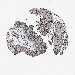

UROTHELIAL CANCER - Protein expressioni

A mouse-over function shows sample information and annotation data. Click on an image to view it in a full screen mode. Samples can be filtered based on level of antibody staining by selecting one or several of the following categories: high, medium, low and not detected. The assay and annotation is described here.

Note that samples used for immunohistochemistry by the Human Protein Atlas do not correspond to samples in the TCGA dataset.

Antibody stainingi

Antibody staining in the annotated cell types in the current human tissue is reported as not detected, low, medium, or high, based on conventional immunohistochemistry profiling in selected tissues. This score is based on the combination of the staining intensity and fraction of stained cells.

Each image is clickable and will lead to virtual microscopy that enables deeper exploration of all samples and also displays staining intensity scores, fraction scores and subcellular localization as well as patient and tissue information for each sample.

Antibody CAB018364

Staining

High

Medium

Low

Not detected

Intensity

Strong

Moderate

Weak

Negative

Quantity

>75%

75%-25%

<25%

None

Location

Nuclear

Cytoplasmic/membranous

Cytoplasmic/membranous,nuclear

Urothelial carcinoma, Low grade

Urothelial carcinoma, High grade